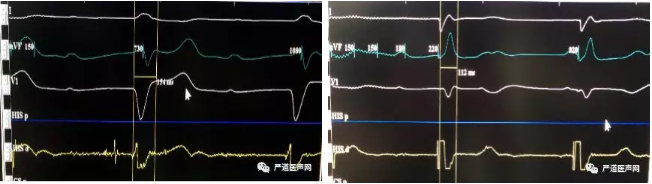

术前心电图&术后心电图

因病人靶静脉成角畸形,电极进入十分困难,即便使用了鞘中鞘技术,也未成功,病人又频发室速,为了尽快缩短手术时间,顾翔教授当机立断,将手术方案进行调整,准备植入3830导线,将导线植入在病人的左束支区域,进行起搏,这种手术方法也是当下最先进的生理性起搏疗法,随即鲍正宇主任、陈福坤博士开始进行手术准备。在团队的努力下,很快导线植入完成,将术前154ms的QRS波缩短到112ms,测得导线参数:阈值0.5v/0.4ms,感知12mv,阻抗653Ω,手术十分成功,学员们也纷纷给顾翔教授团队点赞。

术后4天的超声心动图显示EF值已恢复到57%,并且病人已经顺利出院。